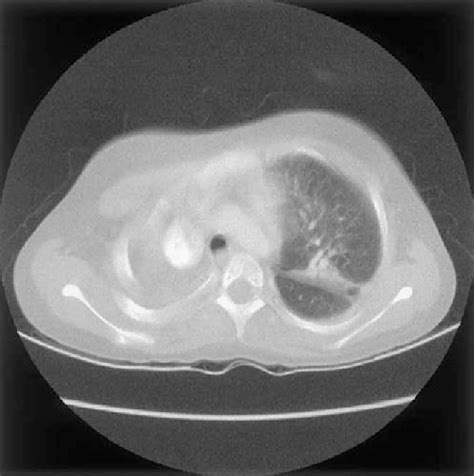

Alright guys, let’s talk about how doctors play detective to figure out if someone has a Nocardia infection . Because, as we’ve seen, the symptoms can be a bit vague and mimic other diseases, diagnosis isn’t always straightforward. The first and most crucial step is suspicion. If a patient presents with symptoms suggestive of infection, especially if they have risk factors like a weakened immune system or exposure to soil, doctors will start thinking about Nocardia. The gold standard for diagnosis is microbiological culture . Samples are taken from the suspected site of infection – this could be sputum from the lungs, pus from a skin abscess, cerebrospinal fluid from the brain, or even tissue biopsies. These samples are then sent to the laboratory where microbiologists try to grow the Nocardia bacteria. This isn’t always easy because Nocardia can be slow-growing, and they require specific culture media and incubation conditions. Sometimes, special techniques are needed to help the bacteria grow, like using modified techniques to isolate them from other bacteria present in the sample. Once Nocardia is successfully cultured, it can be identified using various laboratory methods, including Gram staining, acid-fast staining (remember those waxy walls?), and biochemical tests. Molecular methods, like PCR (polymerase chain reaction), are also increasingly being used for faster and more accurate identification. Imaging studies play a vital role too. Chest X-rays or CT scans can help visualize lung involvement, showing infiltrates, abscesses, or nodules. MRI or CT scans of the brain are essential for detecting brain abscesses. These imaging findings, combined with clinical presentation and laboratory results, help paint a clearer picture. It’s a multi-pronged approach, really. Sometimes, the diagnosis can be tricky, and it might take a few tries to get the right sample or the right culture conditions. Histopathology, the examination of tissue under a microscope, can also provide clues, showing characteristic inflammatory patterns and sometimes even the presence of the bacteria. Susceptibility testing is also a critical part of the diagnostic process. Once Nocardia is identified, the lab will test which antibiotics are most effective against it. This is super important because Nocardia can be resistant to certain drugs, and choosing the right antibiotic early on can make a huge difference in treatment success and preventing complications. So, it’s a combination of clinical suspicion, careful sample collection, specialized laboratory techniques, advanced imaging, and antibiotic susceptibility testing that allows us to finally unmask these elusive Nocardia infections. It’s a real team effort between the doctors, nurses, and lab scientists to get to the bottom of it.